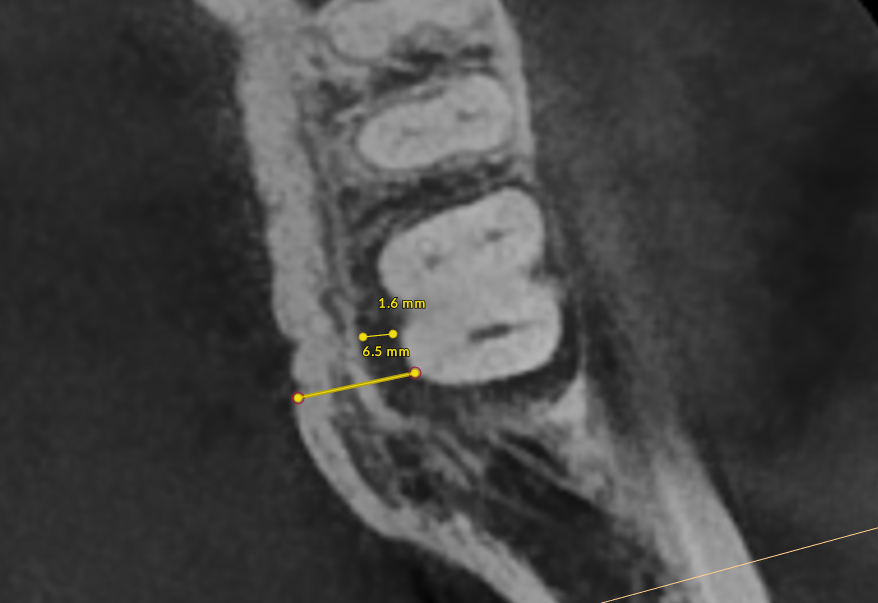

Bone thickness and shape: Bacteria on your teeth can only cause bone destruction within about 1.5 mm of where they sit, referred to as their "sphere of influence." When the surrounding bone is thin or roots are very close together, bacteria can destroy the bone completely, leading to gum recession and more exposed tooth surface. In these cases, non-surgical therapy is often sufficient. When bone is thick, bacteria can only destroy part of it, creating craters or "moats" around the tooth. These craters cannot be fully cleaned with non-surgical treatment and typically require surgery to correct.

- X-Rays (Radiographs): X-rays show the pattern and extent of bone loss. We can see whether bone has been lost evenly (horizontal loss) or whether craters and vertical defects have formed. This pattern directly determines which type of treatment you need.

Step 4, Osseous Surgery (if needed): For pockets that remain deep, surgery gives us direct access to clean root surfaces and reshape or rebuild bone.